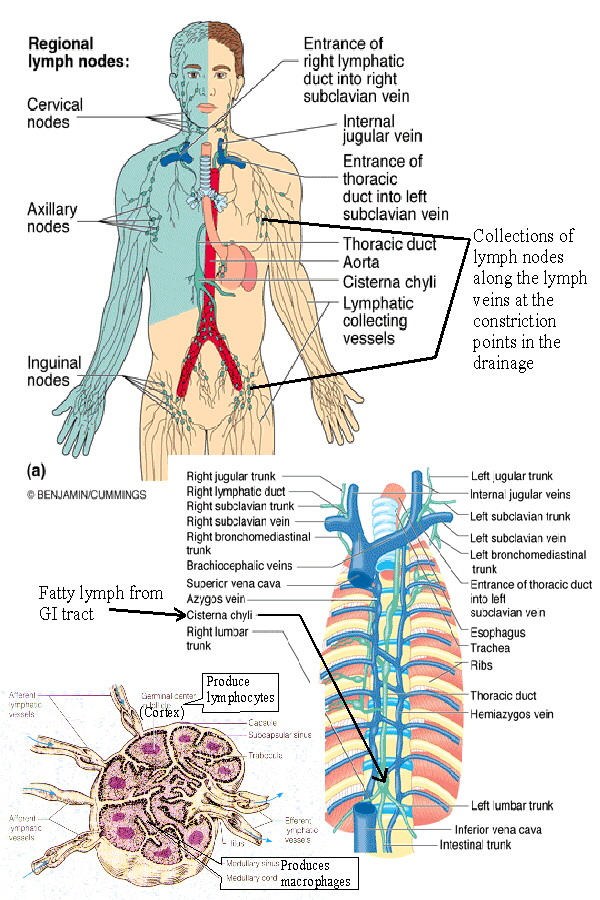

Map Of Lymph Nodes In Human Body

mungfali.com

mungfali.com

The Lymphatic System | BIOL 141 | Thoracic, Lymphatic, Lymphatic System

www.pinterest.com

www.pinterest.com

lymph lymphatic nodes system abdominal wall lymphatics superficial functions thoracic trunk vessels located ducts major direction veins anterior parts structure